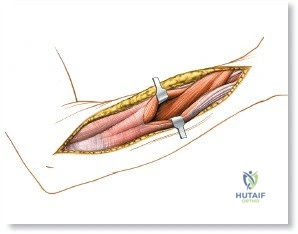

Make a straight or gently curved incision beginning at the anterior flexor crease of the elbow, just lateral to the biceps tendon. Extend this incision distally toward the styloid process of the radius. The exact length and placement of the incision are dictated by the specific pathology; the approach is highly modular, and often only the proximal, middle, or distal third of the incision is required.

Superficial Surgical Dissection and Internervous Plane

Incise the deep fascia of the forearm in line with the skin incision. The initial goal is to identify the medial border of the brachioradialis as it courses down the forearm. It is a common pitfall to search for this border too far laterally. At the level of the elbow, the brachioradialis is expansive and extends almost halfway across the anterior forearm. It is surprisingly easy to mistake the plane between the brachioradialis and the extensor carpi radialis longus for the correct intermuscular plane.

With the forearm fully supinated, identify the broad insertion of the supinator on the anterior aspect of the radius. Incise the supinator directly along the line of its insertion onto the bone. It is critical to detach the muscle by dividing its insertion sharply at the bone, rather than splitting the muscle belly, which would risk cutting the PIN.

Proceed with strict subperiosteal dissection, elevating the supinator laterally off the bone. This is one of the rare instances in orthopedic surgery where the safety gained by staying in a subperiosteal plane completely outweighs the theoretical vascular damage to the bone caused by periosteal stripping. The elevated supinator muscle belly now acts as a protective cushion for the PIN.

Retractor Placement and Fixation Technique

Once the proximal radius is exposed, great care must be taken with retractor placement. Never place Hohmann or levering retractors blindly around the posterior surface of the radial neck. Because the PIN may touch the bone posteriorly in up to 25% of patients, a posteriorly placed retractor can easily crush the nerve against the radial cortex. Instead, use gentle right-angle retractors or place retractors only on the anterior and lateral aspects of the bone, utilizing the elevated supinator as a shield.

For fracture fixation, a dynamic compression plate or locking compression plate is applied to the volar surface of the radius. The volar surface provides a flat, mechanically advantageous surface for plating and allows for excellent soft tissue coverage by the overlying muscle bellies upon closure. Ensure that the natural radial bow is meticulously restored during reduction to guarantee full postoperative pronation and supination.